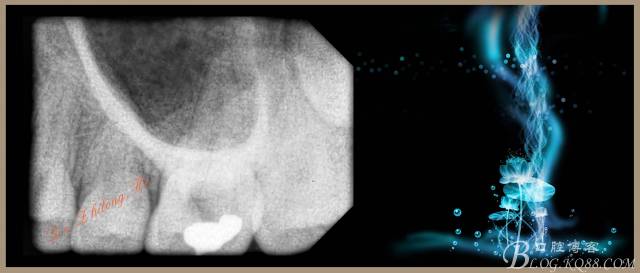

檢查:#26PO可見大面積黑色充填物,腭側(cè)充填物脫落少許,缺損深及髓腔,探(+++),叩(-),冷試驗敏感。X-ray示PO充填物近髓腔,根尖周無明顯異常。

2、手用#15K銼疏通根管+測量WL:P19.5mm,DB、MB、MB217mm。

4、試主尖,側(cè)壓充填法根充,拍根充片,聚羧酸鋅暫封。